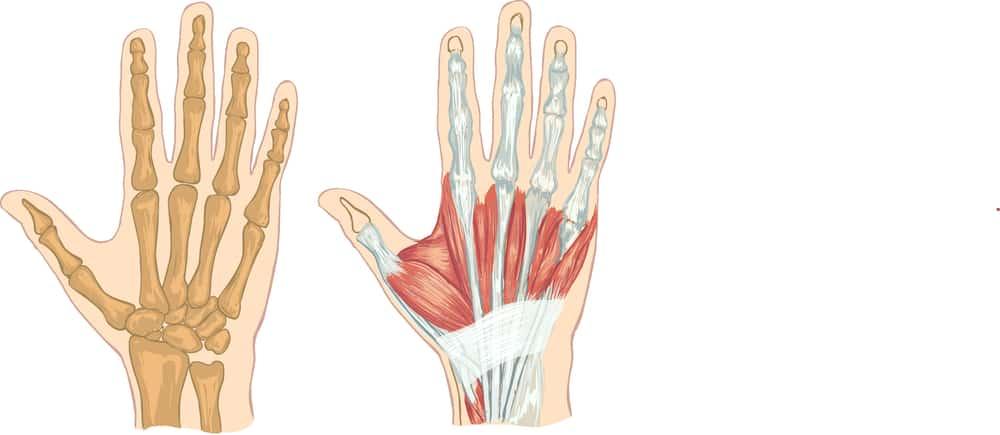

2. Hệ thống cấu tạo xương bàn tay

Hệ thống cấu tạo xương bàn tay khá phức tạp. Trong đó, tay của mỗi người chúng ta có đến 27 xương với 8 xương cổ tay, 5 xương bàn tay và 14 xương ngón tay. Cấu tạo bàn tay cụ thể qua hệ thống xương này như sau:

Cấu tạo xương bàn tay

Lòng bàn tay (phần giữa bàn tay) có 5 xương còn gọi xương bàn ngón, tương ứng với 5 chữ số từ I-V, đều thuộc phân loại xương dài. Mỗi đốt xương này gồm có phần thân (body), nền (base) và chỏm (head). Nền để khớp với xương cổ tay và xương bàn ngón bên cạnh (trừ đốt xương số I).

Cấu tạo xương ngón tay

Mỗi xương ngón tay có 3 đốt theo thứ tự từ trên xuống là đốt gần, giữa và xa. Riêng ngón tay cái thì chỉ có 2 đốt. Tương tự như xương đốt bàn tay, mỗi xương đốt ngón tay cũng gồm nền, thân và chỏm. Trong đó nền để tiếp khớp với xương ở trên và chỏm để tiếp khớp với xương ở dưới trừ chỏm của các đốt xa không tiếp khớp mà tạo thành hình móng ngựa.

4. Các nhóm cơ, dây chằng và gân bàn tay

Bên cạnh hệ thống xương, khớp, khớp nối tinh vi và phức tạp thì còn có nhiều nhóm cơ, gân và dây chằng trong cấu tạo bàn tay:

- Cơ là cấu trúc giúp bàn tay thực hiện các động tác co duỗi và cử động của xương bàn tay.

- Các dây chằng là các mô sợi giúp liên kết các khớp trong bàn tay lại với nhau.

- Các vỏ bọc là cấu trúc hình ống bao quanh một phần của các ngón tay.

- Gân đóng vai trò kết nối các cơ ở cánh tay hoặc bàn tay với xương để cho phép cử động.